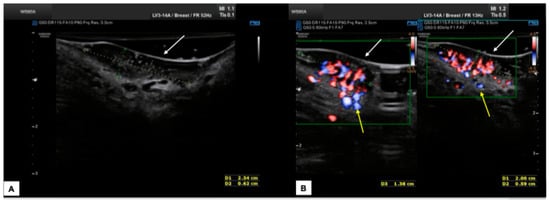

7.1. Benign Vulvar Lesions